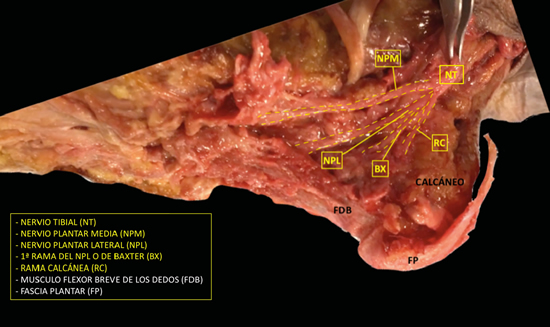

Figura 2. Imagen de disección del nervio tibial y sus ramas.